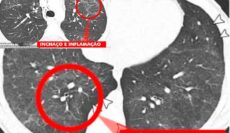

24. QUAL É O TIPO DE LESÃO PREDOMINANTE OBSERVADA NOS PULMÕES?